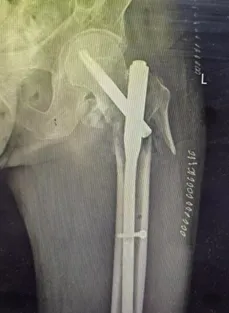

MDT讨论异常激烈,麻醉方案成为争议焦点。骨科鲁增辉副主任建议行微创PFNA内固定术,争取早期活动机会;呼吸与危重症医学科张红军副主任强调须全程护航呼吸功能;重症医学一科郭玉琪主任预备好术后转入ICU的监护支持;麻醉手术科张涛元主任指出,全身麻醉风险极高,而椎管内麻醉因患者自身条件复杂,操作难度与风险同样突出。

手术当日,预案启动。麻醉团队成功完成高难度的腰硬联合麻醉穿刺,麻醉生效后,患者生命体征被严密维持在稳定区间。骨科团队随即接力,在鲁增辉副主任带领下,以微创PFNA内固定术快速、精准地完成骨折复位。呼吸、重症团队全程值守。整个手术仅耗时约一小时,出血少,未发生呼吸循环意外,展现了一场多学科精密配合的典范。